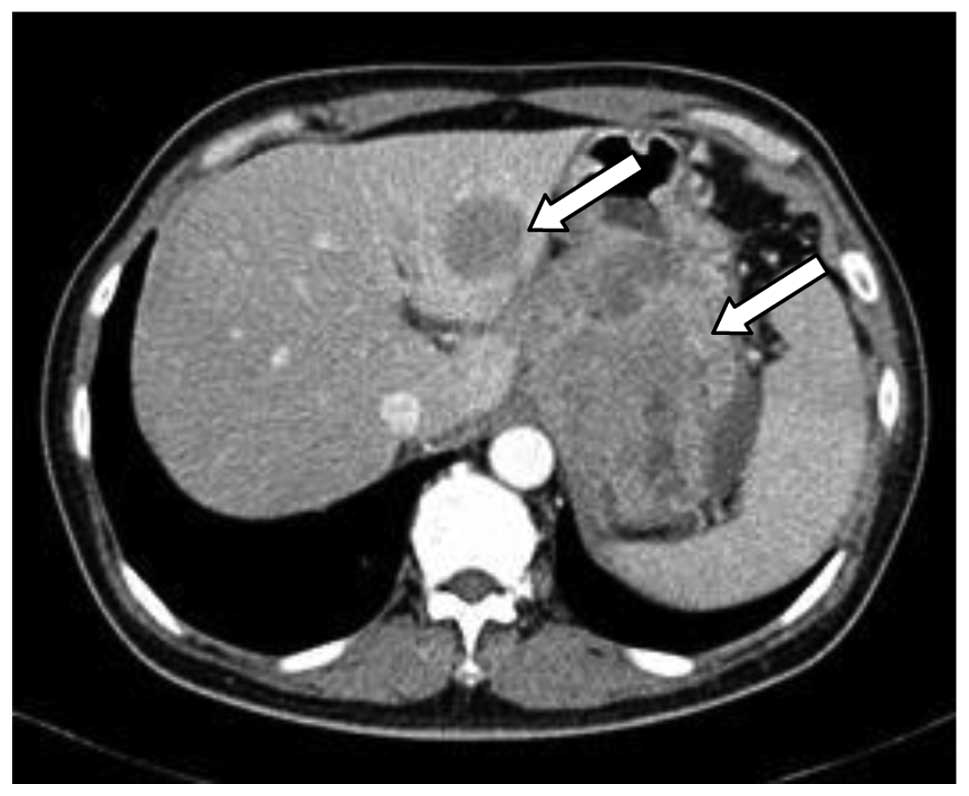

Screening for stomach cancer there are a number of rare conditions that increase your risk of getting stomach cancer including a condition called hereditary diffuse gastric cancer hdgc. The ct scan can help determine the extent stage of the cancer and if surgery may be a good treatment option. You will have a ct scan of your stomach chest and the area between your hips pelvis to find out where the cancer is and whether it has spread.

It is sometimes called computerized tomography or computerized axial tomography cat. Mris use strong magnetic fields and radio waves to produce detailed images. Ct scans can also show the organs near the stomach such as the liver as well as lymph nodes and distant organs where cancer might have spread.

The whole appointment can take up to an hour and a half depending on which part of your body they are scanning. Petct scans help doctors determine the stage of the disease and whether it has spread. Ct scans show the stomach fairly clearly and often can confirm the location of the cancer.